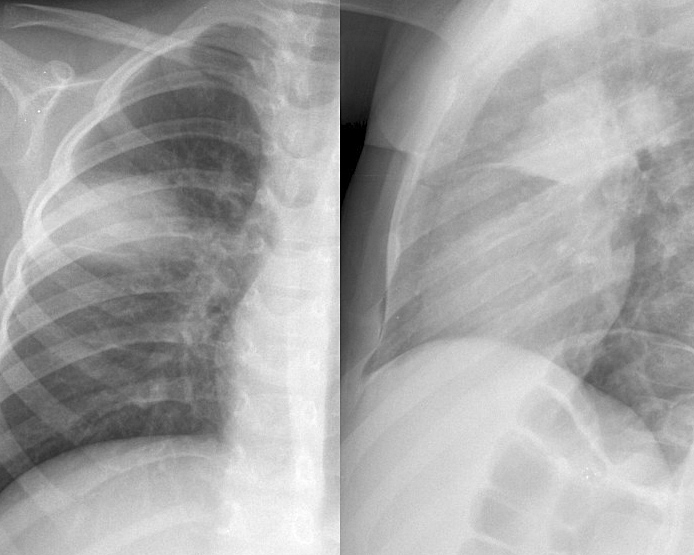

Pneumonia

Round pneumonia different case

Round pneumonia

different case